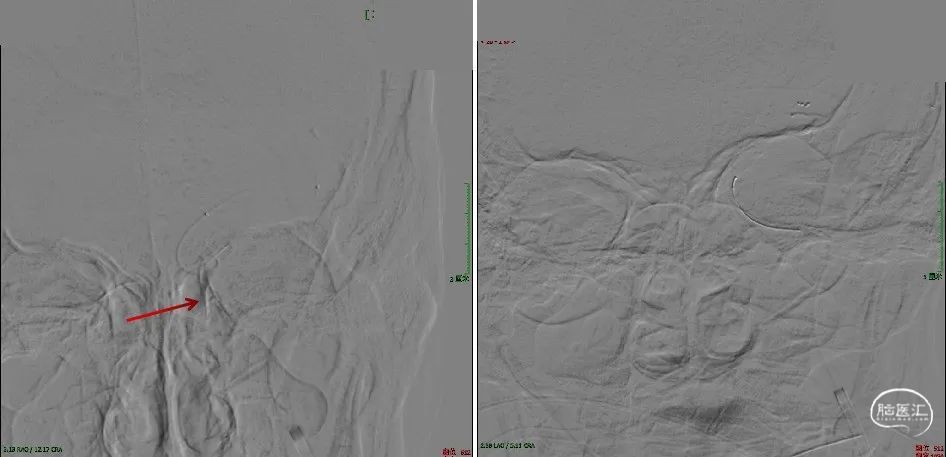

急诊DSA:微导管于LICA-C2段造影见血栓近端所在,明确患者为LICA起始段次全闭塞合并远端栓塞的串联病变。

首先处理起始段狭窄-使用球囊(2×15mm、3×15mm、5×20mm)分3次逐渐扩张颈内动脉起始段。

SWIM技术取栓:半松球囊状态下Neuron Max 6F长鞘顺势送至C2段建立通路。